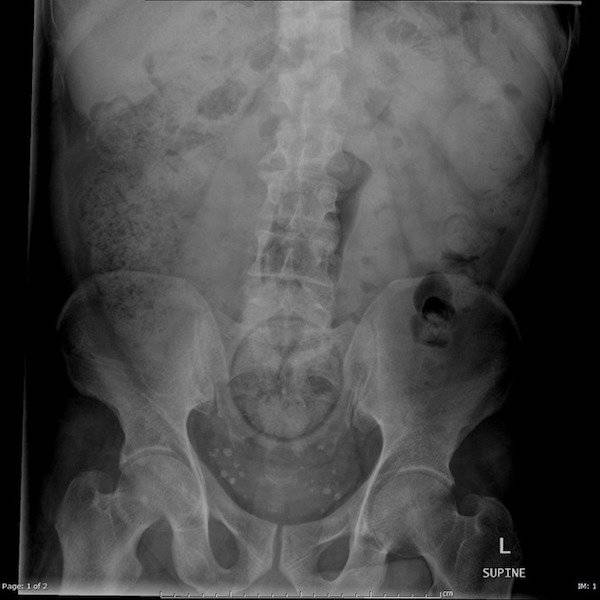

Lääkärit katsoivat nämä röntgenkuvat ja joutuivat hieraisemaan silmiään: 22 eksoottista kuvaa

Röntgenkuvat voivat paljastaa tärkeitä yksityiskohtia ihmisen terveydestä. Joskus ne havaitsevat kuitenkin myös asioita, joita ihmiskehon sisällä ei todellakaan kuuluisi olla.

Lääkärit saivat varmasti hieraista silmiään, kun he katselivat näitä röntgenkuvia. Toki joissakin tapauksissa tiedettiin jo, mitä etsiä, mutta osa tuli varmasti yllätyksenä.

Yksi erikoisimmista oli naisen vatsassa oleva käärmä, kuinka se on voinut sinne joutua?!

Näiden kuvien jälkeen voin todeta, että olen nähnyt kaiken!